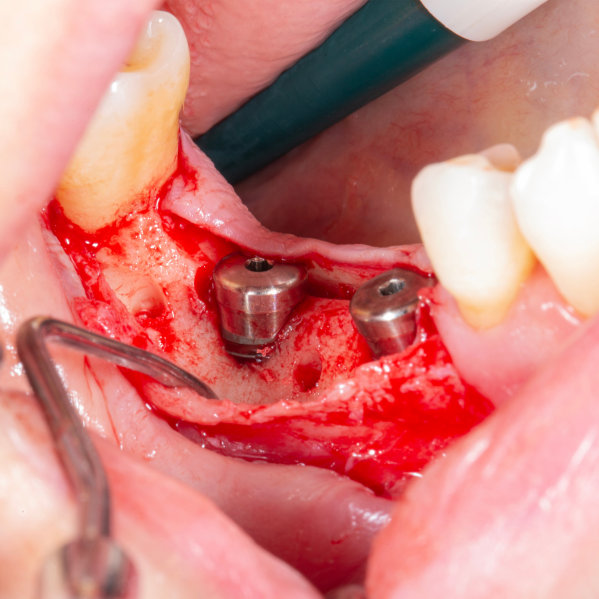

Diş çekiminin yıllar önce yapılmış olmasına bağlı olarak ince kemik varlığında implant ve kemik grefti uygulandı.